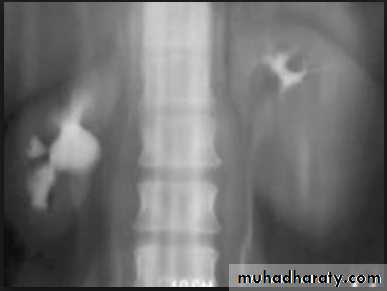

l.V.U. findings:

-Plain film may be useful in demonstrating calculi. -After contrast injection: Acutely obstructed kidney shows a dense nephrogram (dense opacification of the renal parenchyma).

excretion of contrast (opacification of the collecting system which may take many hours) ,

then the level and degree of obstruction can be determined as dilated pelvi-caliceal system and ureter are followed down to the point of obstruction (point of hold up).